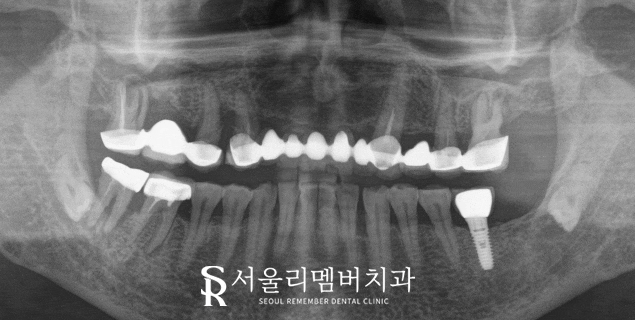

서울대입구역 치과 초진 파노라마를 보면

상악에는 브릿지가 자리를 잡고 있었으며

그 밑으로 뿌리 끝 염증이나 충치,

치주 질환으로 인한 치조골 소실 등

여러 문제들이 동반되고 있었습니다.

비교적 아래쪽은 상황이 괜찮았는데요.

위쪽 치아가 너무 아프다는 말을 하셨기에

이점을 고려하여 계획을 세워야겠네요.

초진 파노라마에서 볼 수 있듯이

치아 내부 문제가 심하게 나타나고 있었으며

치조골 소실까지 이어질 정도로

상황이 좋지 않았습니다.